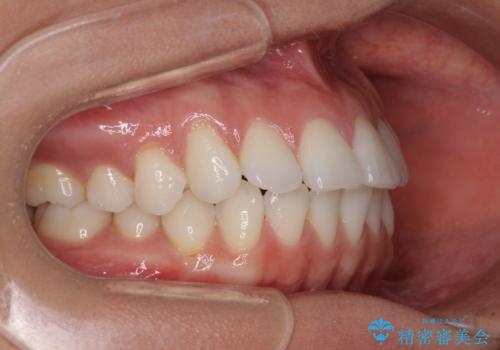

【モニター】インビザラインで口を閉じやすく

- 前に出ている上顎前歯が気になるとのことで来院された患者様です。

インビザラインを用い、IPR(歯と歯の間を削る)と歯列全体を後方に移動させることで、可能な限り前歯の突出感を改善することとしました。

元々の歯列も整っており、横顔の印象の出っ歯ではなかったため、仕上がりに満足できない可能性があると心配しておりましたが、口が閉じやすくなり、患者様には大変満足していただきました。